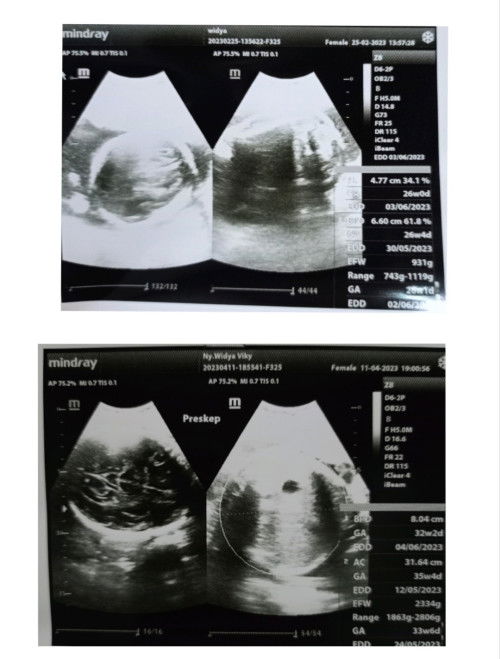

Hi Bund, maaf mau nanya saya kemarin pas USG yang atas kan dikasih tau sama dokternya kalo hpl tgl 3 juni Terus yg bawah saya USG lagi, tapi lupa GK nanya hpl tgl berapa Cara bacanya gimana ya Bund? Soalnya hasil USG atas dan bawah beda Makasih yang udah jawab #seriusnanya #bantusharing #ingintahu